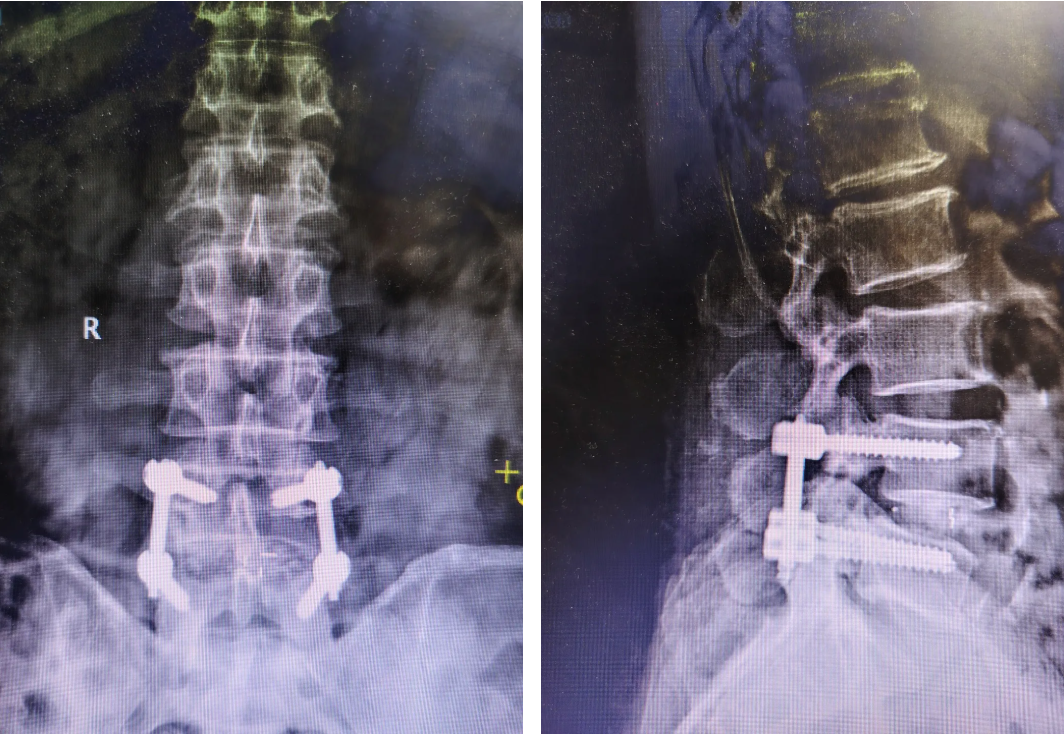

术后

术后效果好,患者腰背部疼痛及下肢麻木症状明显缓解。与传统手术相比,微创优势凸显:术后仅留下2个微小切口,无需长期卧床,术后第2天即可在医护指导下下地活动。目前患者恢复状况良好,已顺利康复出院。

手术在麻醉科等多学科协作下有序开展。术中,医生通过微创通道精准去除压迫神经的骨赘、肥厚黄韧带及病变椎间盘组织,随后在内镜监视下置入融合器,并经皮植入椎弓根螺钉完成内固定,实现椎间融合与脊柱稳定性重建。整个手术过程视野清晰、操作精准,术中出血很少。